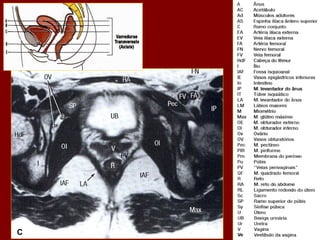

A

B

C

D

E